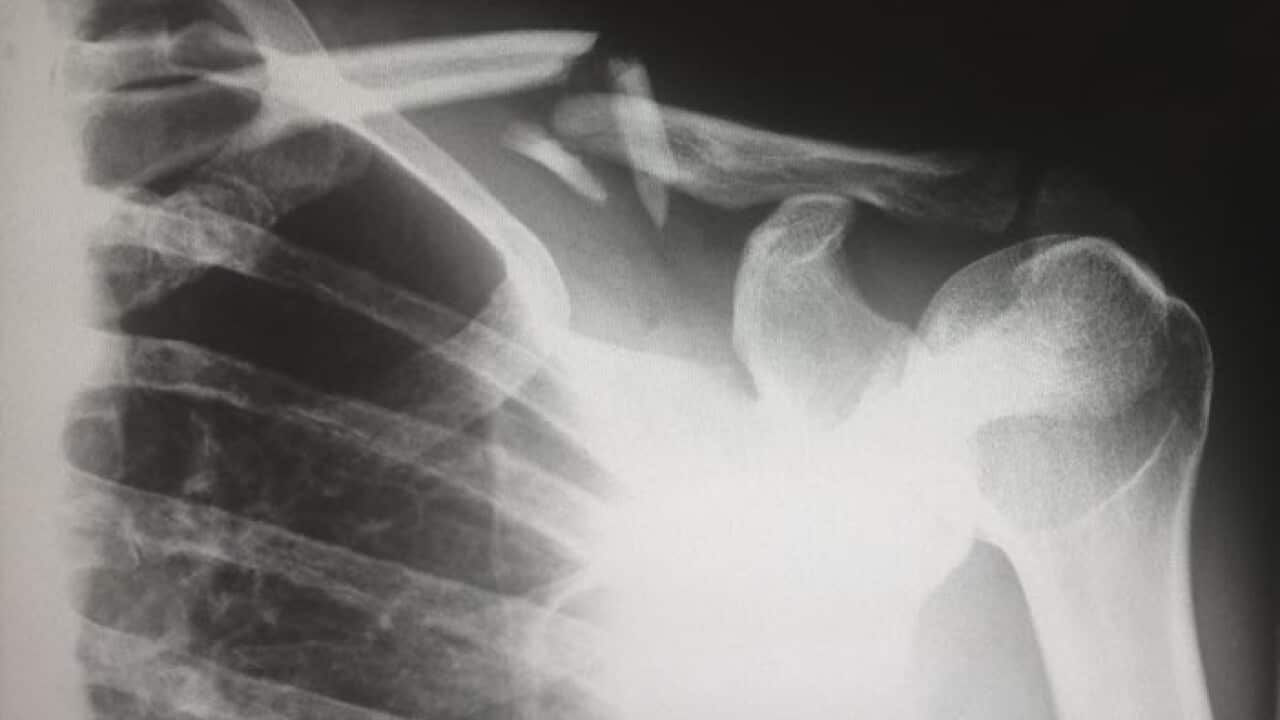

Разлике између oстеопорозе и oстеопеније

У данашњем здраственом додатку говоримо о разликама Остеопорозе и Остеопеније. О статистикама, начинима мерења, узроцима, дијагностиковању као и терапијама Александар Живковић је разговарао са Др Велибором Тодоровићем.